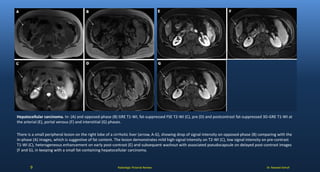

Hepatocellular carcinoma. In- (A) and opposed-phase (B) GRE T1-WI, fat-suppressed FSE T2-WI (C), pre (D) and postcontrast fat-suppressed 3D-GRE T1-WI at

the arterial (E), portal venous (F) and interstitial (G) phases.

There is a small peripheral lesion on the right lobe of a cirrhotic liver (arrow, A-G), showing drop of signal intensity on opposed-phase (B) comparing with the

in-phase (A) images, which is suggestive of fat content. The lesion demonstrates mild high signal intensity on T2-WI (C), low signal intensity on pre-contrast

T1-WI (C), heterogeneous enhancement on early post-contrast (E) and subsequent washout with associated pseudocapsule on delayed post-contrast images

(F and G), in keeping with a small fat-containing hepatocellular carcinoma.